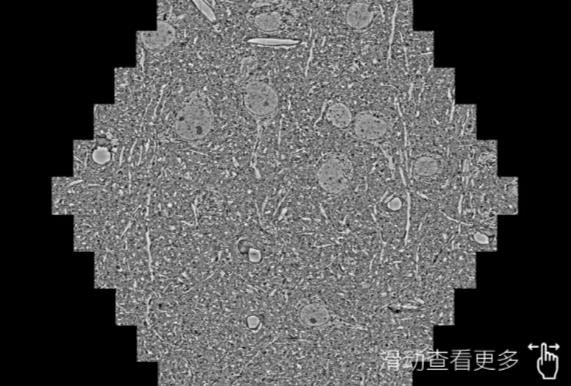

鼠脑切片。左图使用荆州蔡司荆州扫描电镜MultiSEM706对165μmx143pm面积区域成像,耗时仅需1.5秒。右图为鼠脑切片中30μm区域放大效果。样品由芝加哥大学B.Kasthuri提供。

使用蔡司高速荆州扫描电镜MultiSEM对1mm²人脑皮层组织进行高分辨成像,并对其中的各种细胞结构进行三维重构分析。左图展示了2x3mm²组织平面中锥体神经元的三维重构效果。右图显示了局部体积神经元三维重构。图像由哈佛大学chtman实验室提供,渲染图由D. Berger 制作。